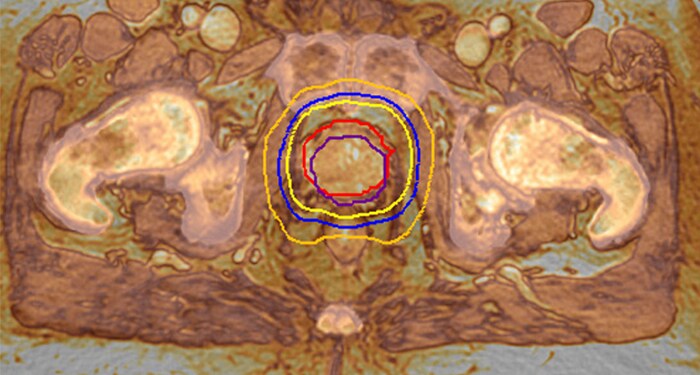

MR-RT XD meets the need for accuracy with advances in image quality, geometric fidelity, and reproducible patient positioning. You acquire high quality MR images in the treatment position, boosting accuracy in target delineation and critical structures.

Highly targeted treatment plans rely on MR imaging performed in the treatment position. With MR-RT XD you acquire high quality MR images in the treatment position, boosting accuracy in target delineation and critical structures.

MR-only radiotherapy planning

MRCAT lets you plan radiation therapy based on one MR exam. By excluding the need for CT, this helps relieve the burden on your clinical resources, reimbursement obligations and budget. And your patient is spared to undergo a second scan – reducing the patient burden.